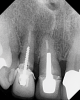

(3.) Radiograph of a loose screw-style metal post.

Figure 3

Today, most post and core restorative treatments employ a prefabricated post made from either metal or fiber. Although the trend has been toward the use of fiber posts, early in the transition from indirect to direct post and core protocols, metal posts were primarily used. Prefabricated metal posts are available in two basic shapes: parallel and tapered. In addition to being highly radiopaque, metal posts are extremely rigid, possessing a high modulus of elasticity of 100 GPa to 200 GPa, and transfer more stress from the coronal aspect to the thinner apical segment.3 Because of the "wedge effect," tapered metal posts can be more threatening to the remaining tooth structure. This was especially true with the early threaded posts, which readily came loose (Figure 3) or resulted in a fractured root.